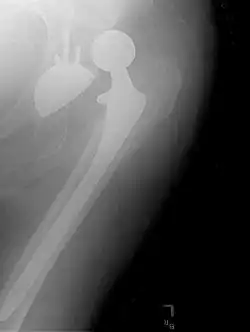

Prothèse totale de hanche

Une prothèse totale de hanche (PTH) est un dispositif articulaire interne qui vise à remplacer l'articulation de la hanche et lui permettre un fonctionnement quasi normal, en tout cas permettant la marche.